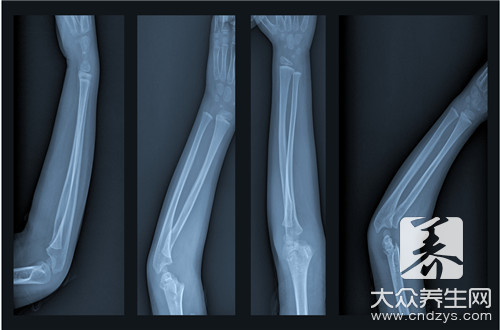

骨折是指骨结构的连续性完全或部分断裂。多见于儿童及老年人,中青年人也时有发生。病人常为—个部位骨折,少数为多发性骨折。经及时恰当处理,多数病人能恢复原来的功能,少数病人可遗留有不同程度的后遗症。

2.固定

骨折复位后,因不稳定,容易发生再移位,因此要采用不同的方法将其固定在满意的位置,使其逐渐愈合。常用的固定方法有:小夹板、石膏绷带、外固定支架、牵引制动固定等,这些固定方法称外固定。如果通过手术切开用钢板、钢针、髓内针、螺丝钉等固定,则称内固定。